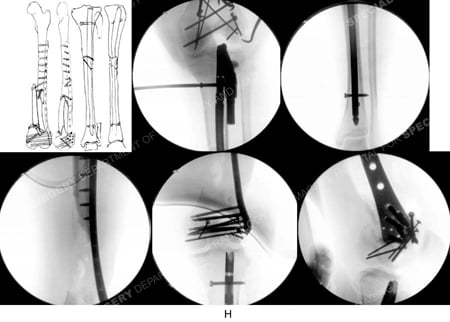

Counterclockwise from top-left; pre-operative plan, fluoroscopic images showing placement of intramedullary nail (IM) for the tibial shaft fracture and locking screws and open reduction and internal fixation (ORIF) of the distal femur fracture with placement of a LISS locking plate and screws.